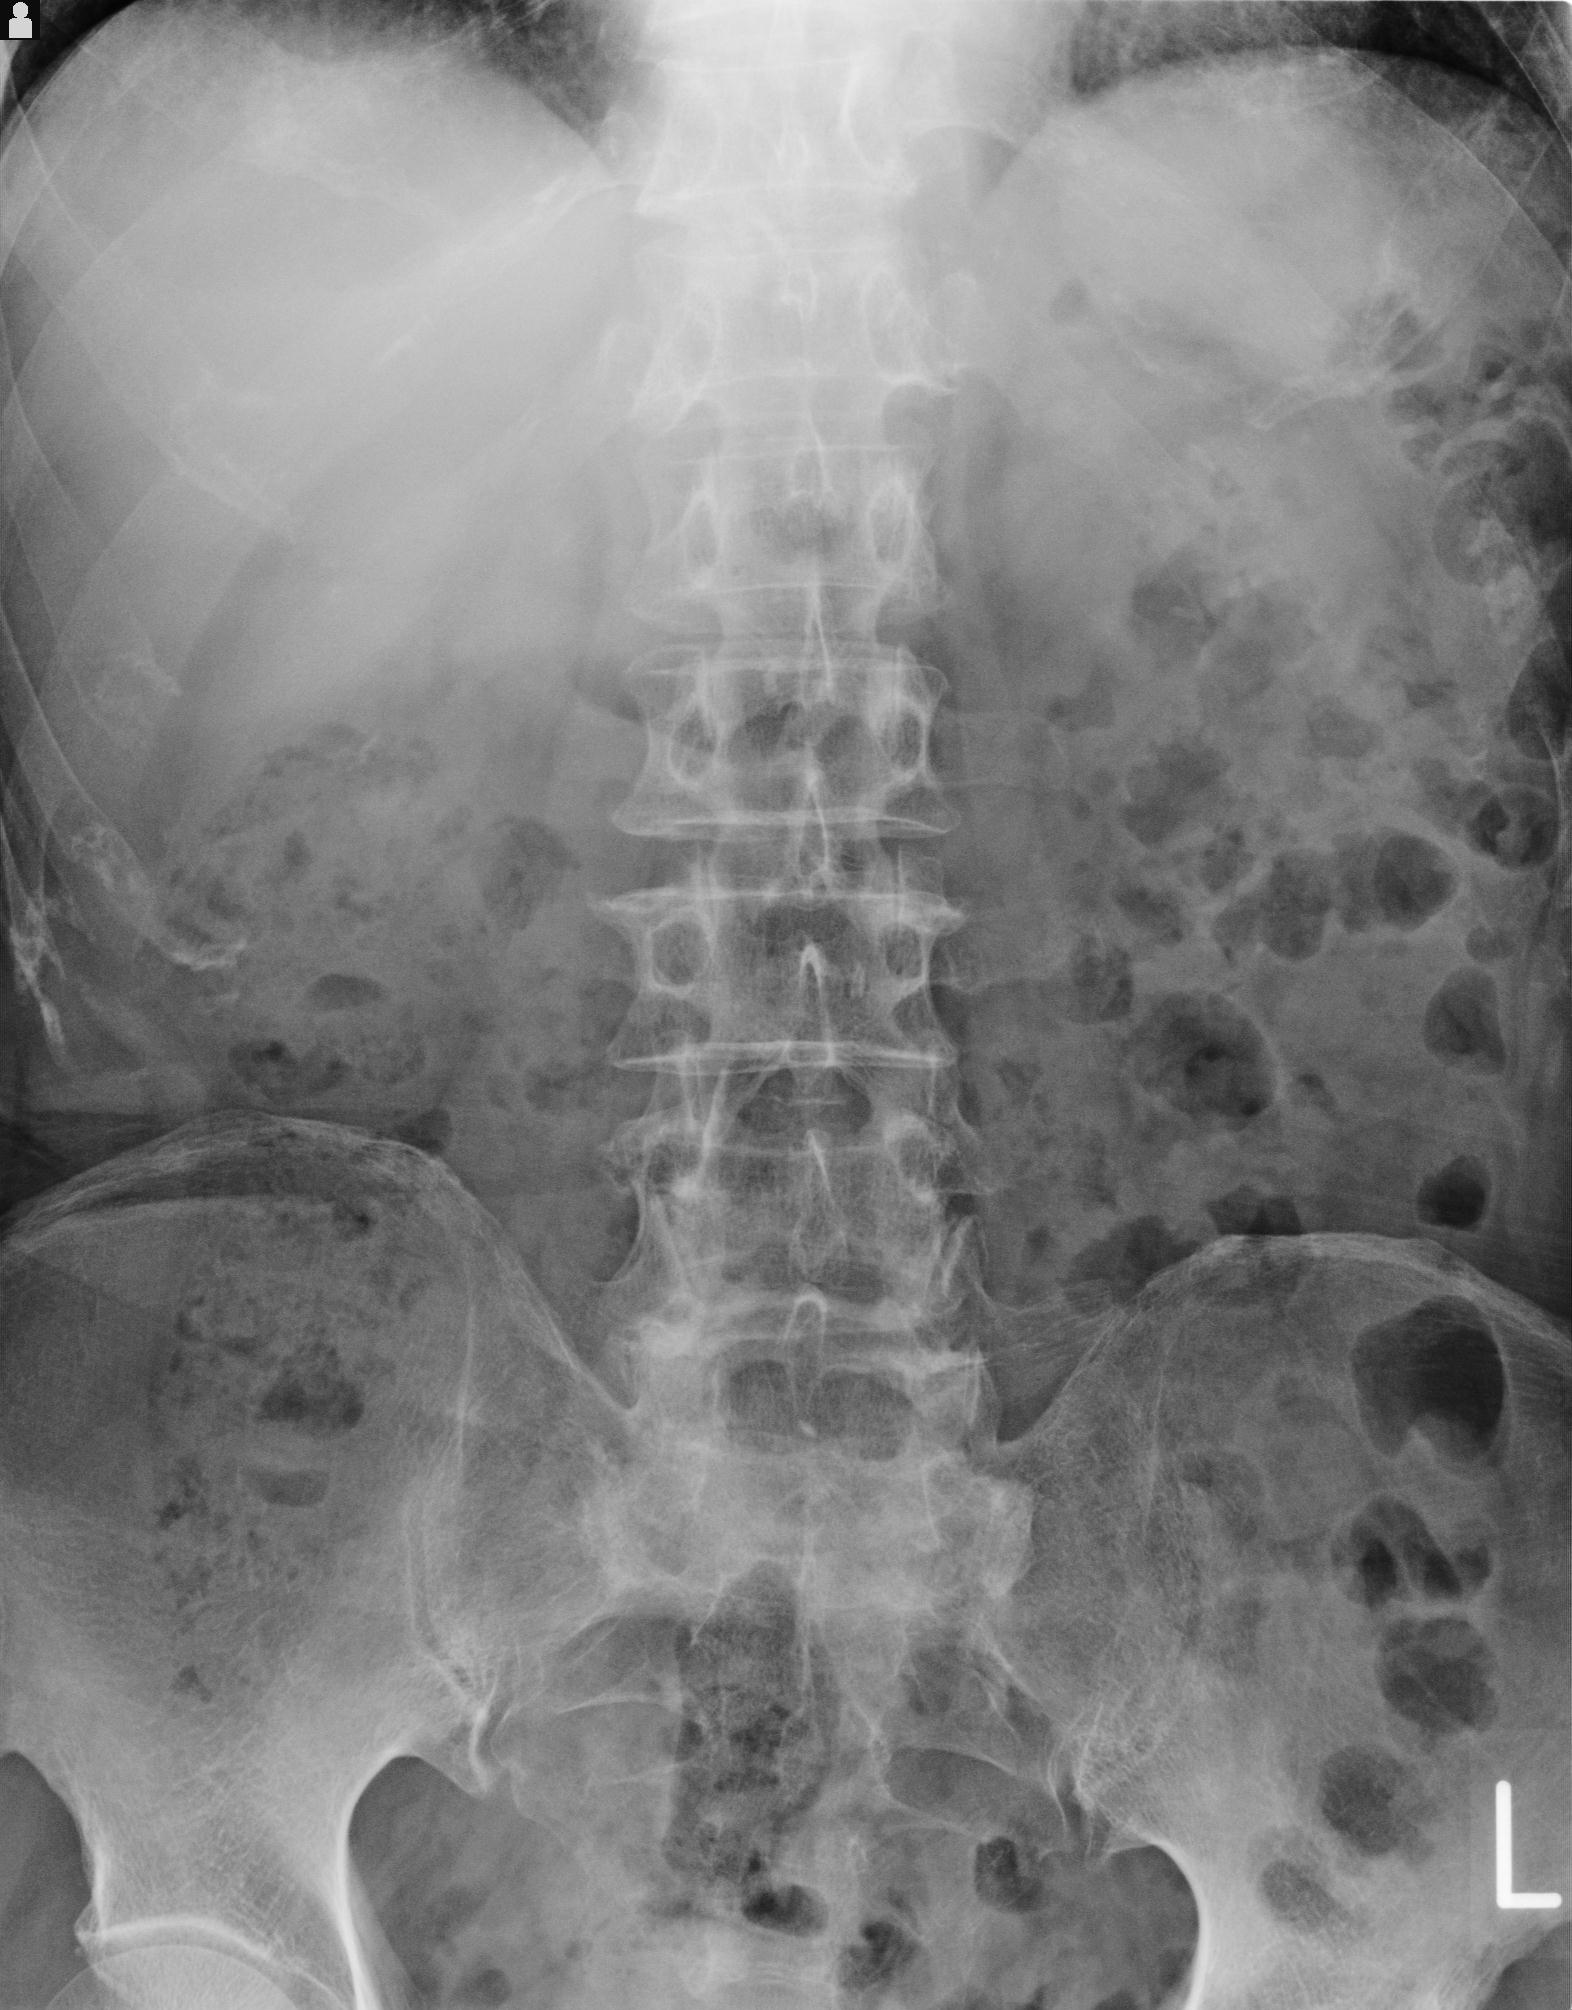

102916 2/1 と 3/22 腰椎 2R 74歳女性 LIFX

100703 1/27 両股正面+軸 1/29 両股正面+軸 94歳女性 パンソンロン

93804 2/9 腰椎 2R 後方固定 67歳女性